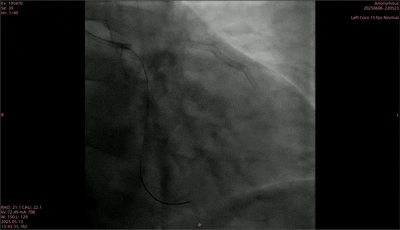

手术过程中,首先于前降支植入2枚药物洗脱支架,重复造影显示狭窄解除。随后,使用2.0mm×15mm规格的预扩球囊对回旋支远段进行预扩张,扩张后直径狭窄程度为25%,血流TIMI 3级,但病变处在预扩后出现B型夹层。后续采用2.0mm×30mm的矩正医疗冠状动脉血管重塑导管,以6atm压力扩张血管,并同步启动激光治疗。最终,术后造影结果显示,狭窄处扩张效果良好,残余狭窄20%,且原夹层消失,血流TIMI 3级,手术圆满完成。

术后